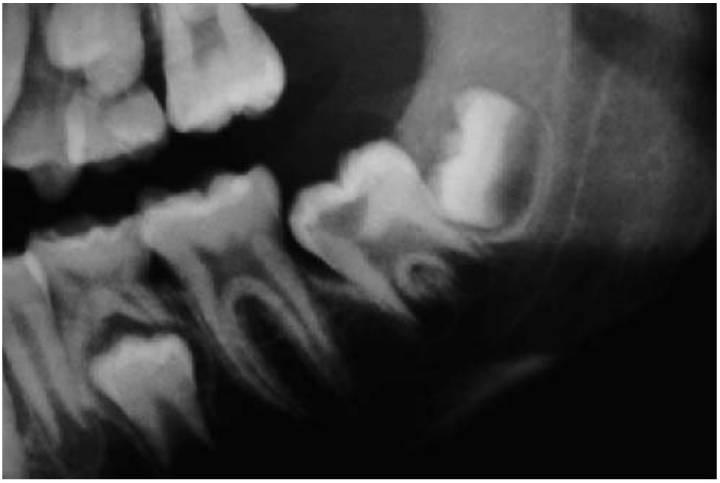

Los dientes supernumerarios surgen como resultado de una geminación de la lámina dental que se produce de forma esporádica o se heredan, como sucede con la displasia cleidocraneal (fig. 9.8).

La forma de los dientes puede recordar a la forma de las piezas normales (diente suplementario), es decir, incisiforme, caniniforme o molariforme; de no ser así, sería cónico o tuberculado.

Habitualmente se presenta como consecuencia del fallo en la erupción de uno o más dientes permanentes y en general presenta formas cónicas o tuberculadas.

- Erupción fallida o ectópica de un diente permanente (fig. 9.8B).

- A menudo erupcionan dientes cónicos que se pueden extraer con mucha facilidad (fig. 9.8A).

- Los dientes tuberculados o cónicos invertidos requieren extracción quirúrgica (fig. 9.8D) tan pronto como sea posible para permitir la erupción sin obstáculos del diente permanente.